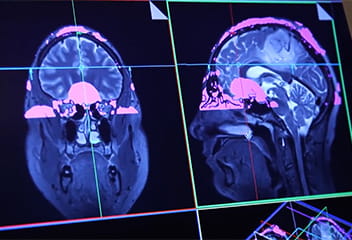

IU School of Medicine has amassed an extensive array of imaging tools for neuroscience research, including multiple MRI and PET scanners, cyclotrons to produce radioactive trace elements, and the capacity to process images and store enormous data files.

These imaging tools provide 3D views of the brain, its structures, abnormalities, and protein compositions— tremendous tools that would be applied to bipolar disorder research.